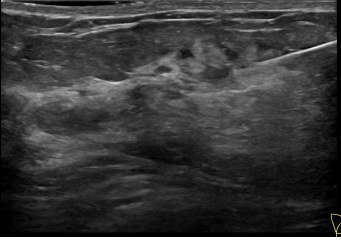

상기환자는 외부검사이상소견으로 정밀검사위해 내원하신 40대초반

여성분으로 의심스러운 우측혹 조직검사 시행해 유방암 진단되었습니다.